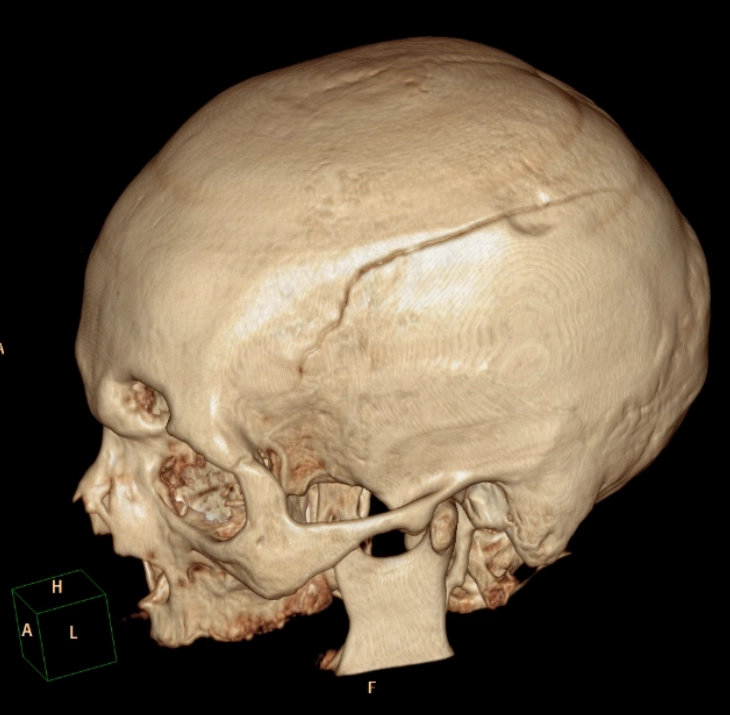

Gãy sương sọ (Skull fractures)

Vỡ lún xương sọ (Depressed Skull Fracture)